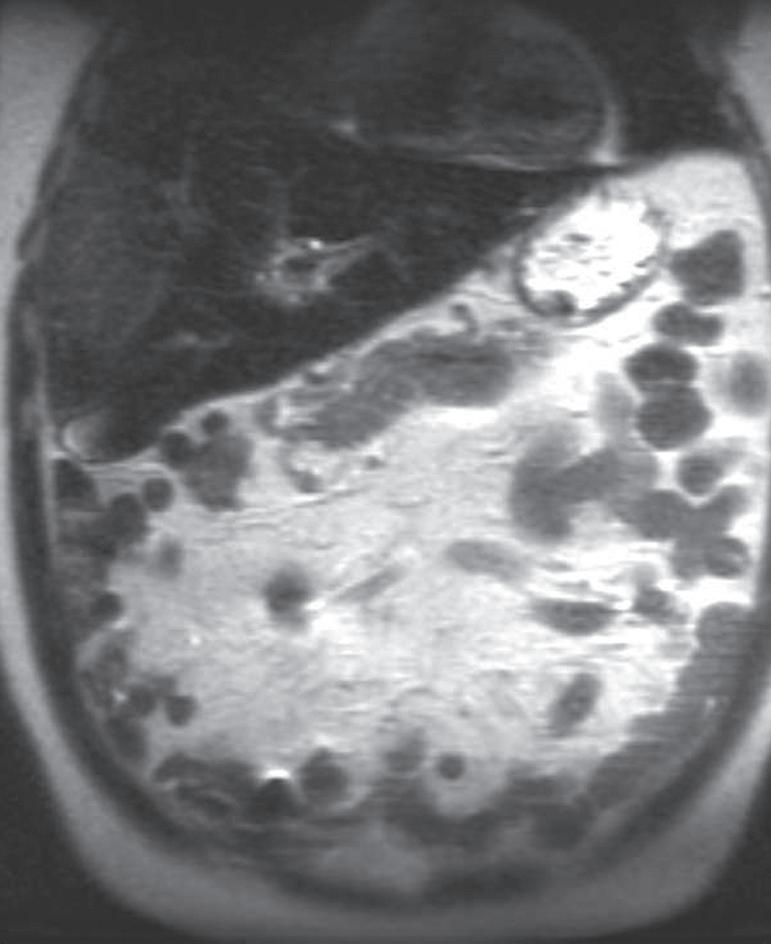

FIG. 1.15 Liver magnetic resonance imaging (MRI) obtained on a 0.3-Tesla system. Axial in-phase (A) and out-of-phase (B) images display relatively markedly diminished signal throughout the liver on the out-of-phase image compared with the in-phase image, indicating fatty infiltration. The axial T2-weighted image (C) reveals a small hyperintense lesion (arrow in C and D), which enhances as seen on the delayed T1-weighted gradient echo image (D), degraded by low signal-to-noise ratio and breathing motion artifact. Axial T2-weighted image obtained on a different patient on a 0.3-Tesla system (E) demonstrates prohibitive artifact distorting the image beyond diagnostic utility, compared with the corresponding image (F) from a follow-up study performed on a 1.5-Tesla short-bore, open-configuration system.

FIG. 1.16 Liver MRI obtained on a 1.5-Tesla system. In-phase (A) and out-of-phase (B) images demonstrate steatosis reflected by relative signal loss on the out-of-phase image. Axial T2-weighted single-shot fast spin-echo (SSFSE) image (C) reveals a small hyperintense lesion (arrow) in the posterior segment of the liver. The axial arterial (D) and delayed (E) images show initial clumped, peripheral, discontinuous enhancement with uniform, persistent enhancement (arrow). Note the higher signal-to-noise (SNR) and improved image quality compared with Fig. 1.15 A–D.